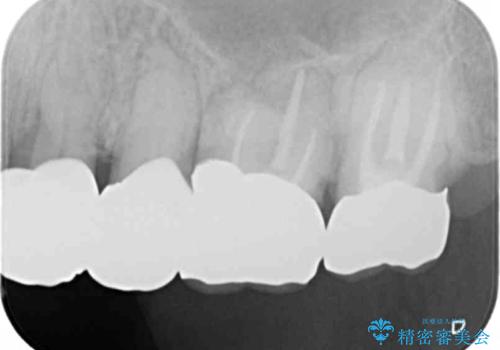

咬合の崩壊 金属床義歯で咬合機能の回復

「大規模な手術は避けたい。」と言う希望を鑑み、インプラントではなく残せる歯の連結セラミッククラウンの作製、金属床義歯を用いてしっかりと咬合機能を回復できるよう治療を進めます。

- 110万円(ジルコニアクラウン×7・仮歯×7 金属床義歯)費用は治療当時の料金となります

年齢と体調を考慮して、インプラントではなく入れ歯で咬合機能の回復を達成する治療計画としました。